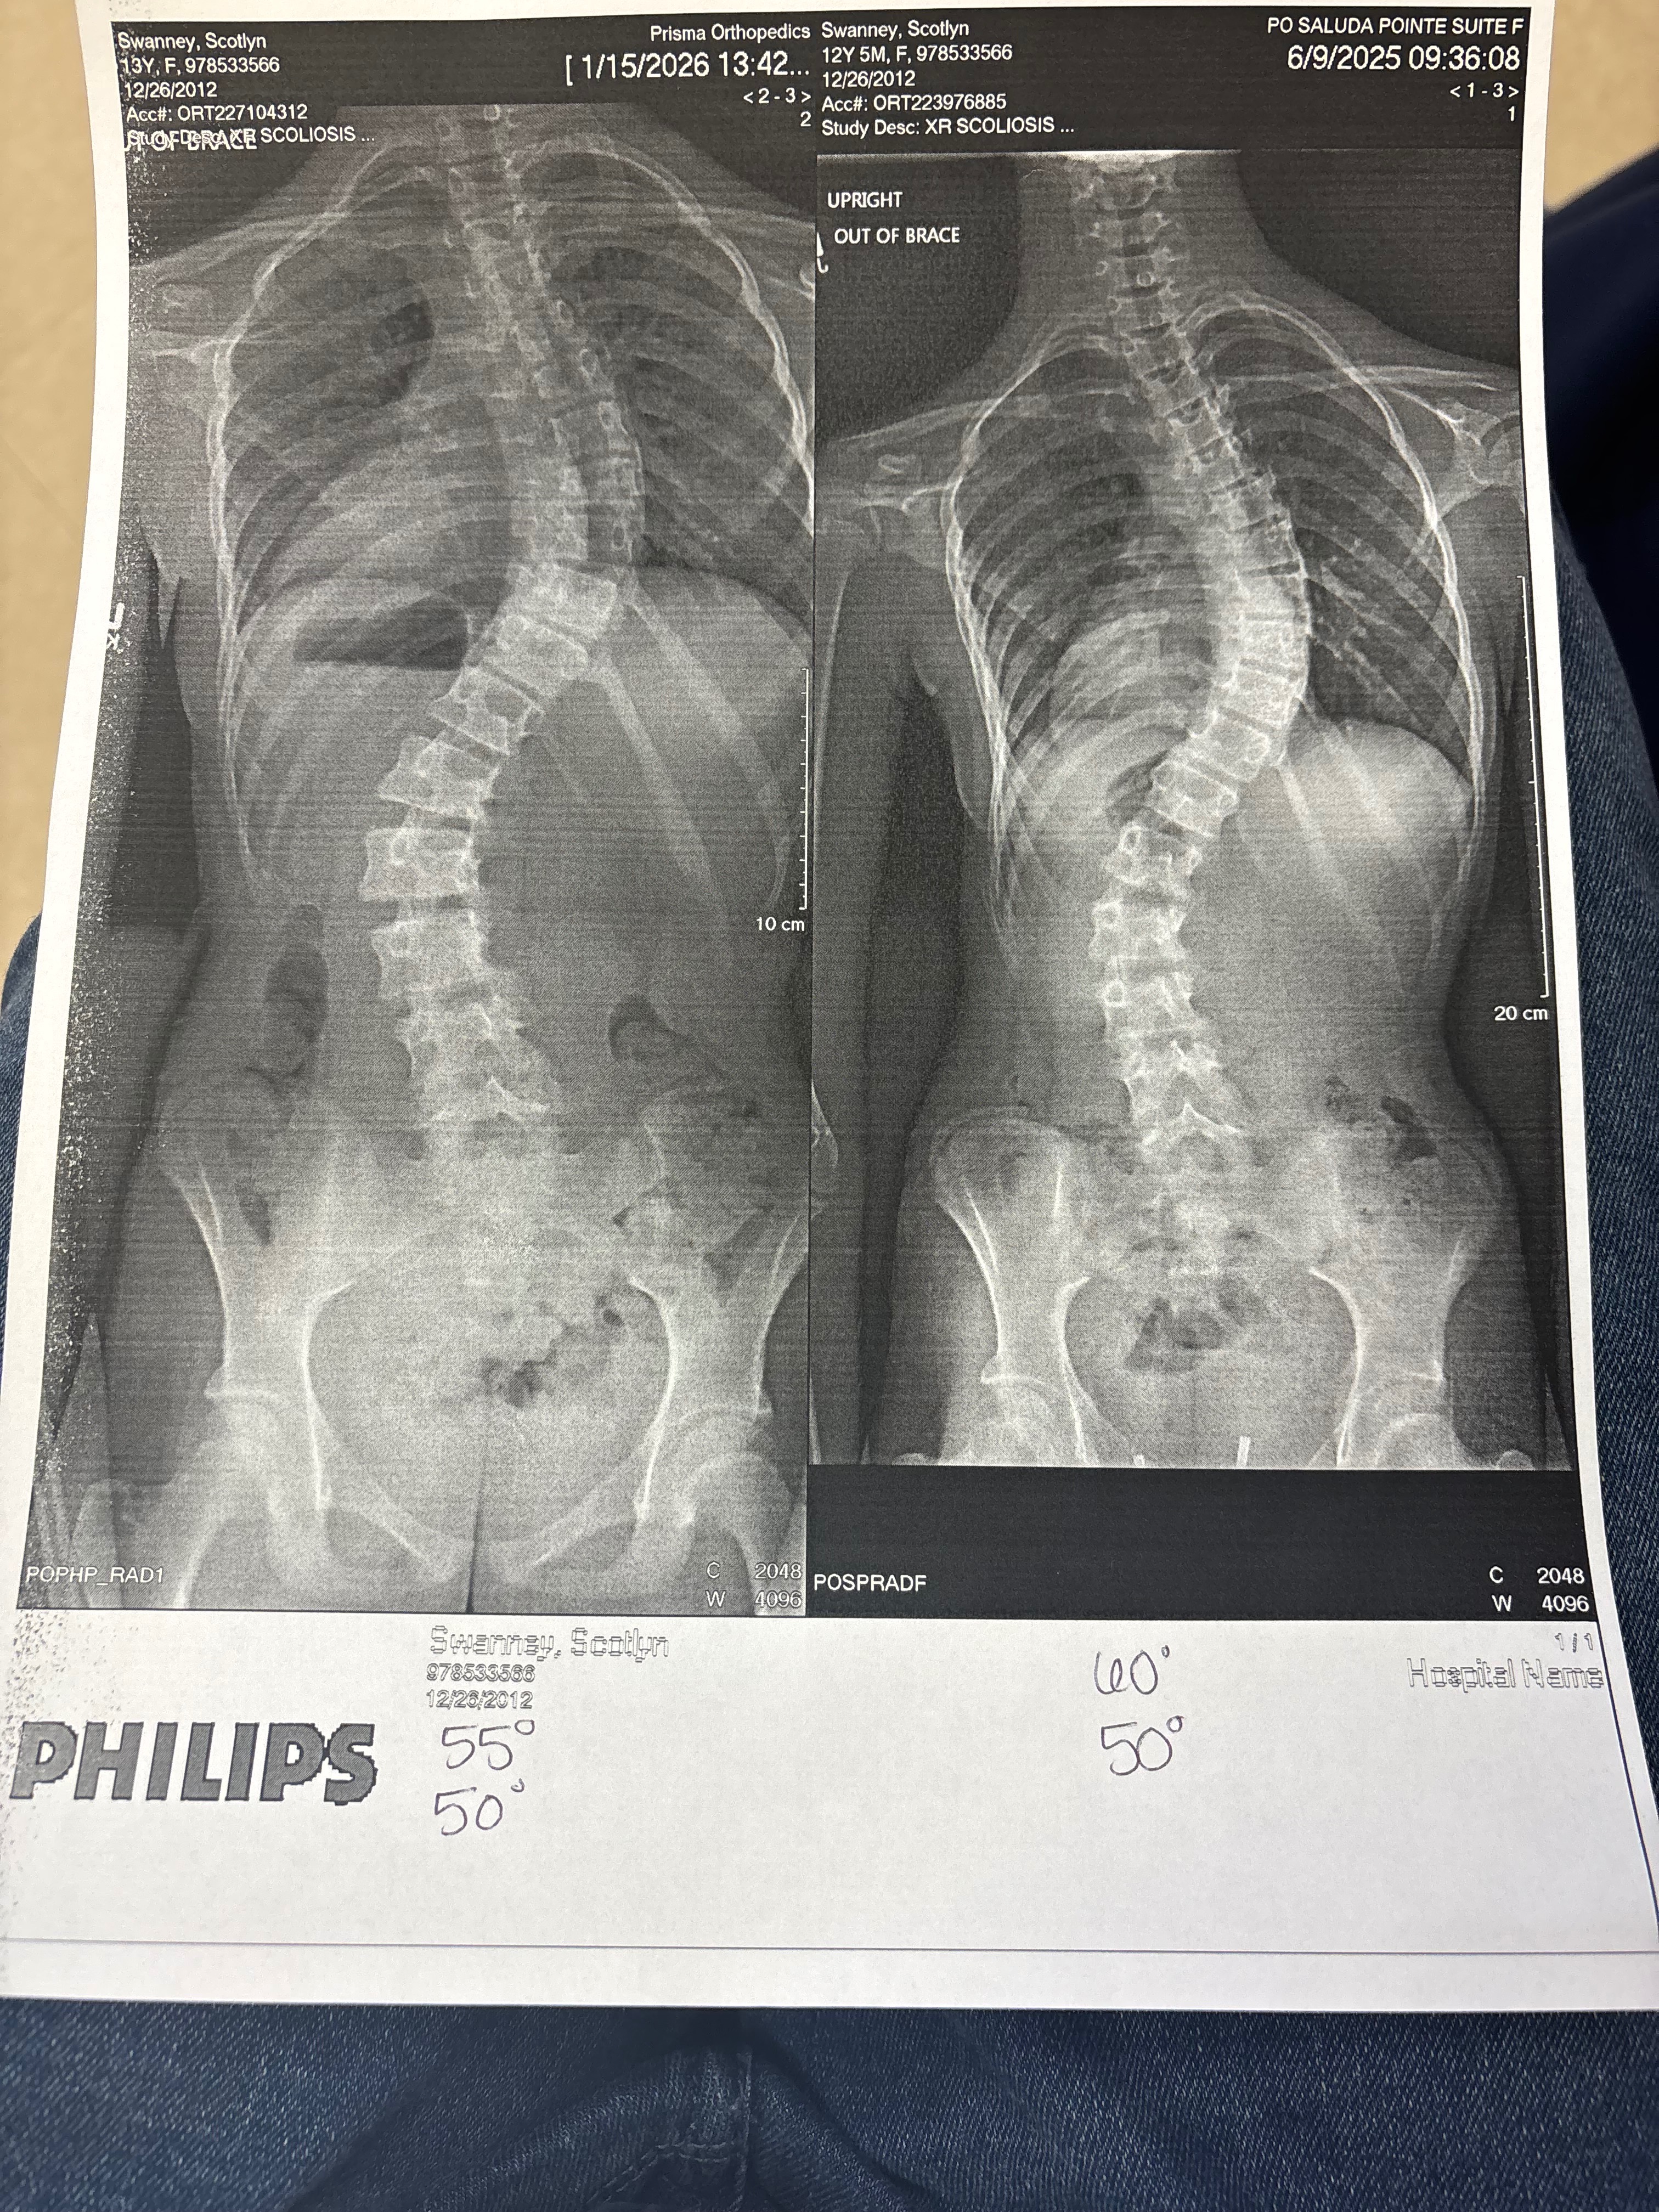

My daughter, Scotlyn, has been diagnosed with severe scoliosis. This condition has progressed quickly, and now surgery is the only option to help her regain comfort and mobility. As a parent, it’s heartbreaking to see her struggle with pain and the limitations this brings to her daily life. We’ve been working with doctors and specialists to find the best path forward, and the upcoming operation is our hope for a brighter, healthier future for Scotlyn.